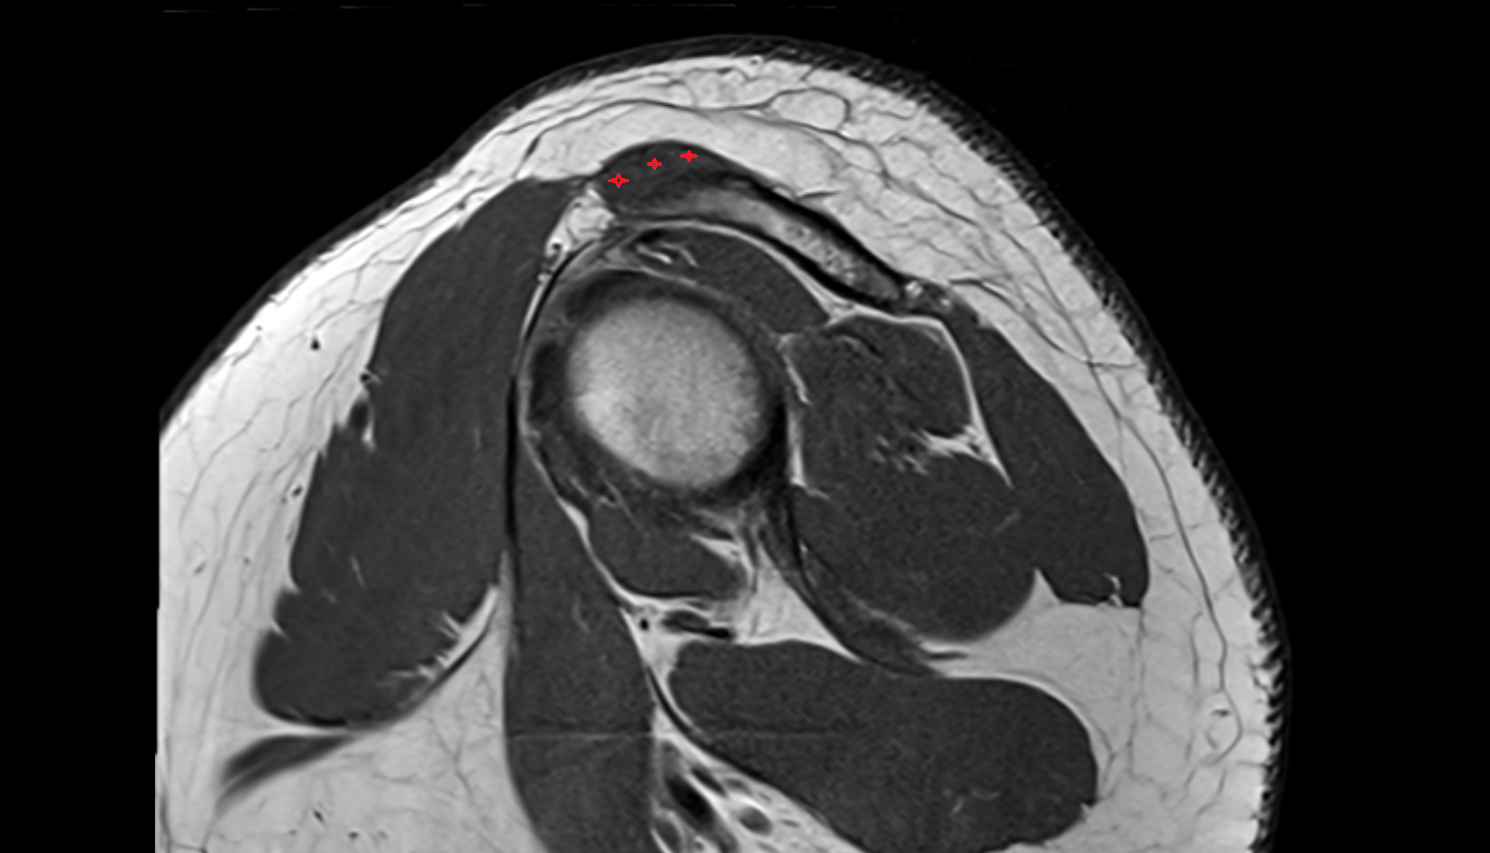

- Supraspinatus tendon

- Subscapularis tendon

- Glenoid labrum

- Subacromial space